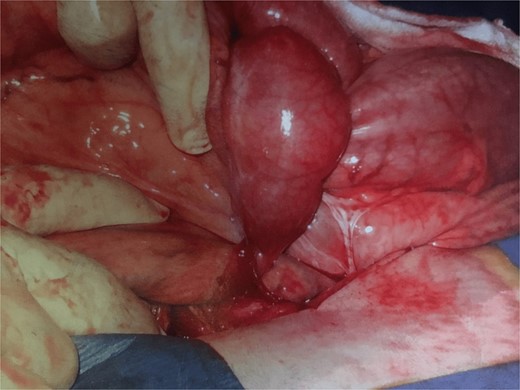

Further exploration revealed a mesenteric adhesive band compressing the herniated bowel and worsening the obstruction (Fig. 1). Approximately 30 cm of necrotic bowel was resected due to ischemia, and blood flow was restored to the remaining bowel (Fig. 2).

This image depicts the surgical field after the division of the mesenteric adhesive bands and the resection of the necrotic segment of the small bowel. The division of the bands has successfully restored blood flow to the remaining healthy bowel. The previously ischemic bowel segment has been removed, and the surrounding tissue shows signs of improved perfusion, indicating successful restoration of circulation.